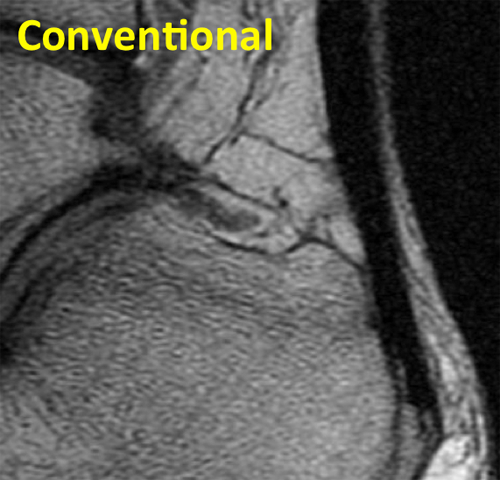

Tendon Conventional

Conventional sagittal MR image of the ankle shows the low signal intensity Achilles tendon.

Tendon UTE

UTE sequence of the ankle shows normal fasciculation (white arrow) in the tendon and a region of tendinosis (orange arrow) that could not be seen on the standard MRI.